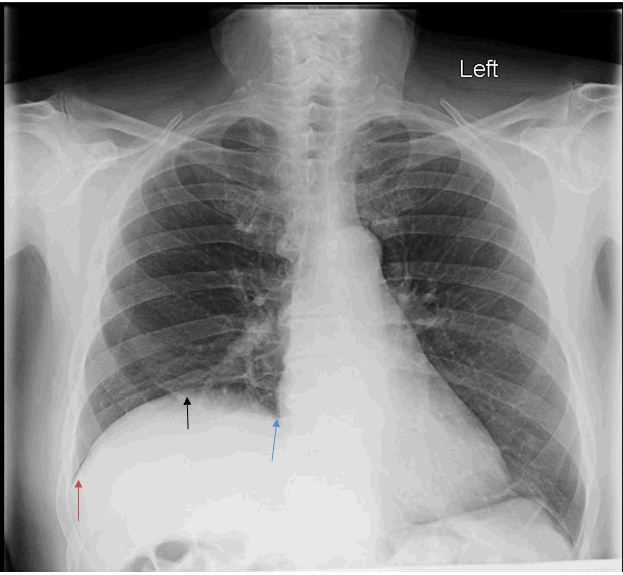

As workup for his dyspnea, the patient underwent pulmonary function testing, which showed a restrictive type of lung disease. A chest radiograph revealed an elevated right hemidiaphragm (Figure 1), which was confirmed by a CT scan (Figure 2). This raised the possibility of right phrenic nerve paralysis as the cause of his symptoms. There was no movement of the right hemidiaphragm observed during a sniff test, (Figure 3) which confirmed the diagnosis.

Figure 1.

Chest radiograph shows significant right hemidiaphragm elevation. No other visible pathology is seen in the lung field. (Black arrow indicates dome of the diaphragm. Red arrow points toward a clear costophrenic angle. Blue arrow shows a clear cardiophrenic angle.)